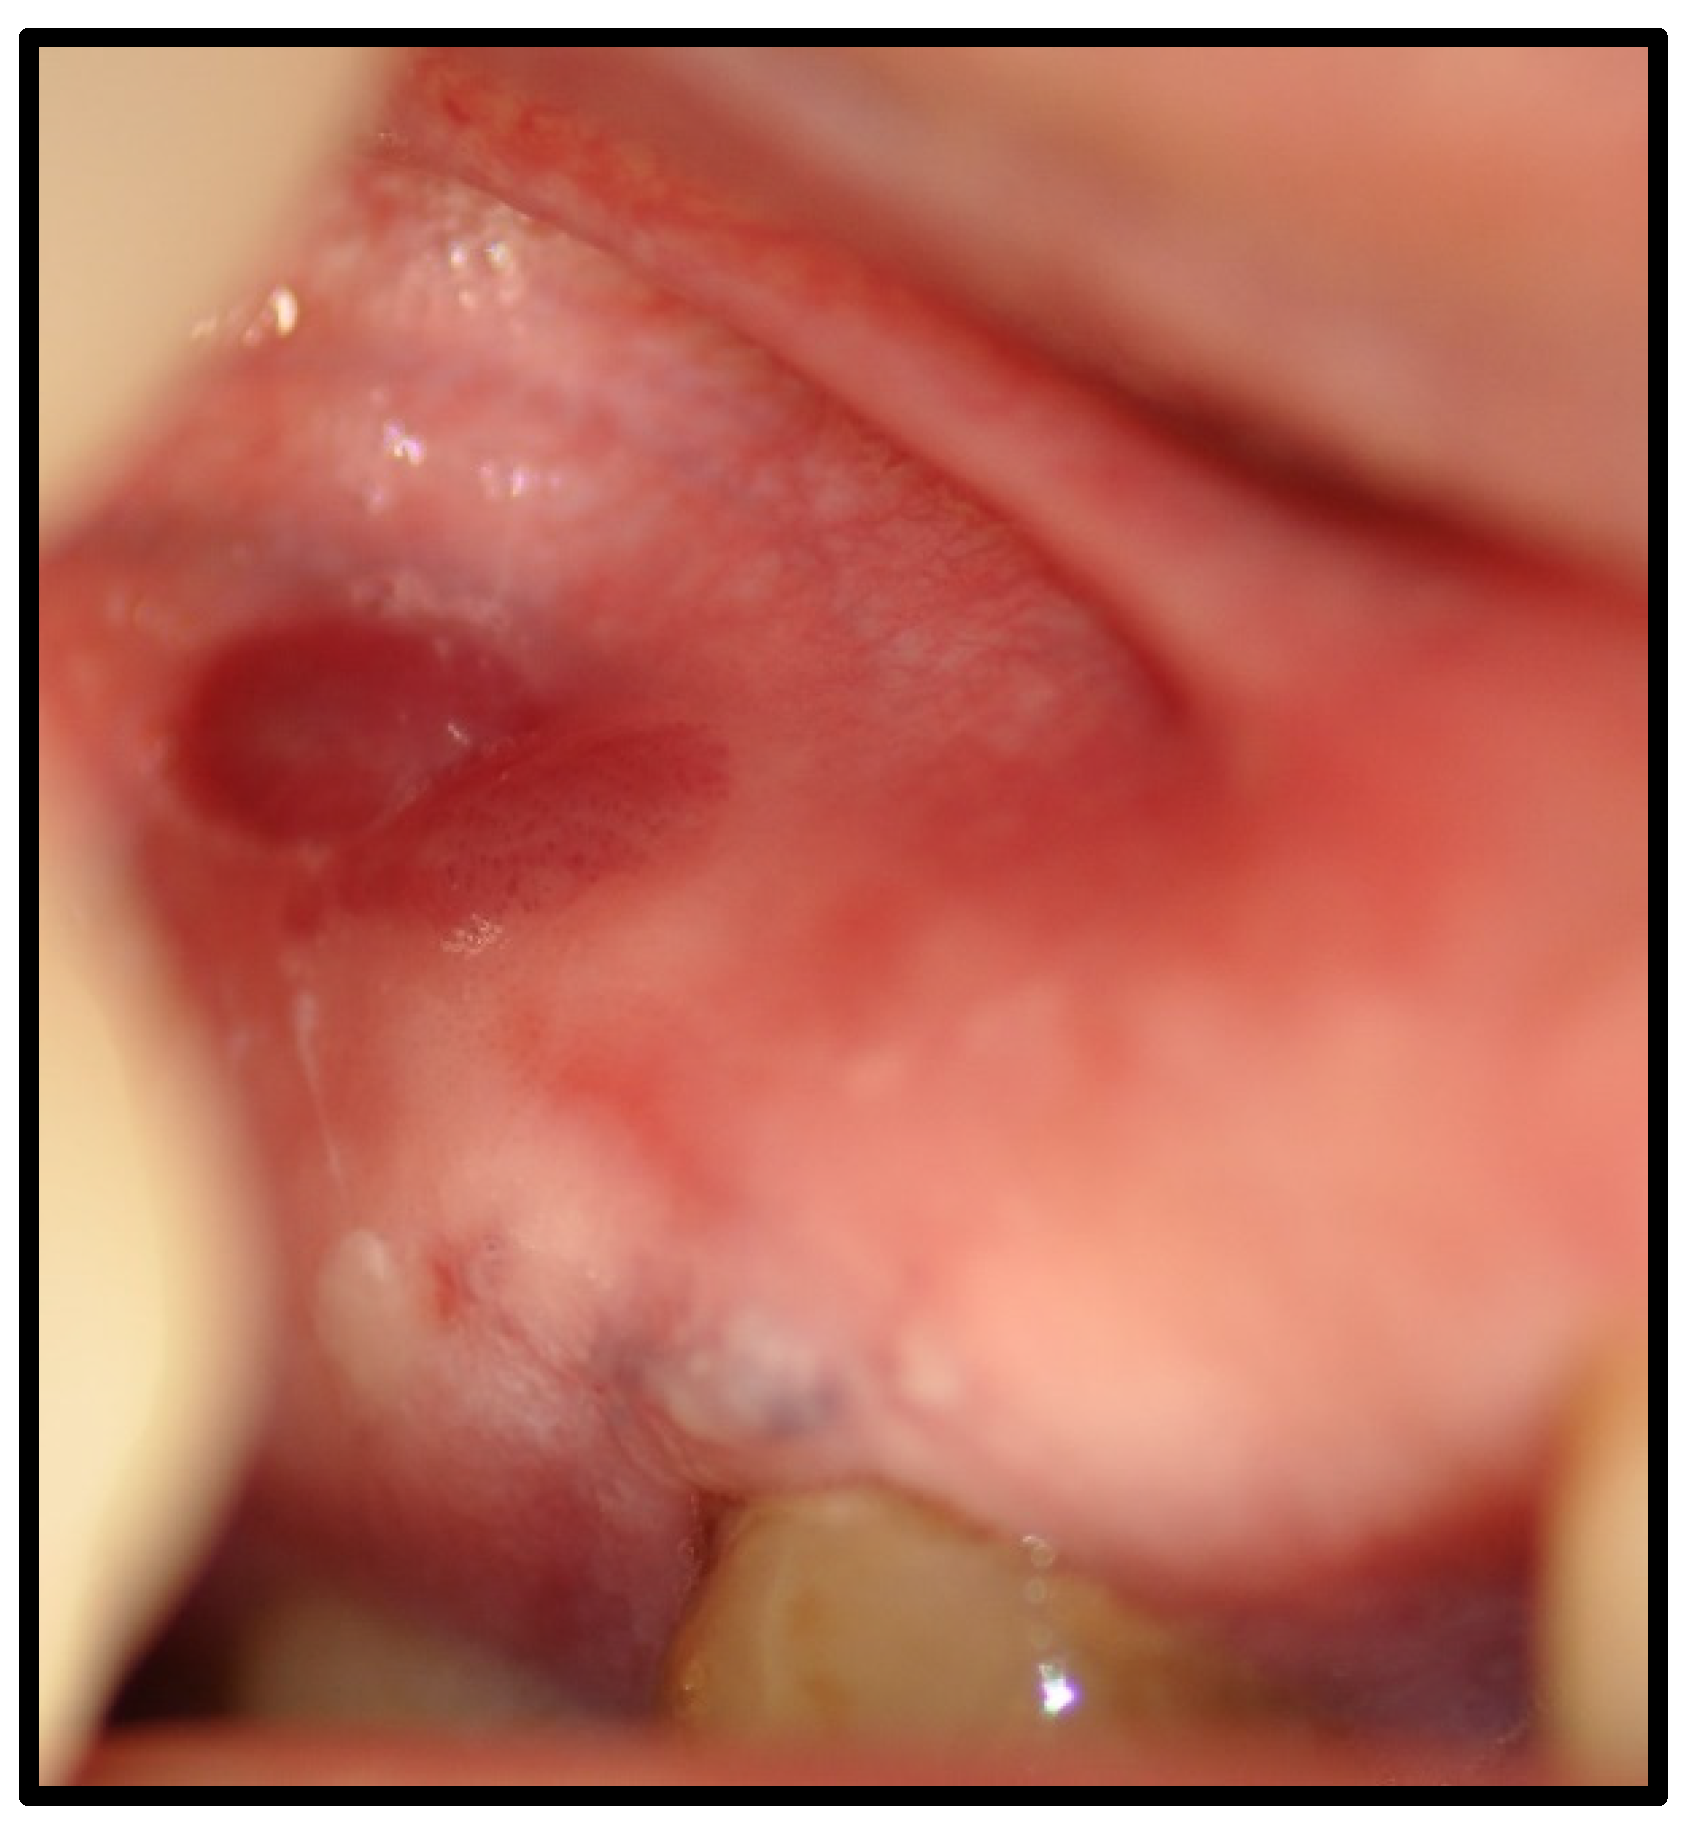

| Benign mucous membrane pemphigoid | 3 | 12.50 | |